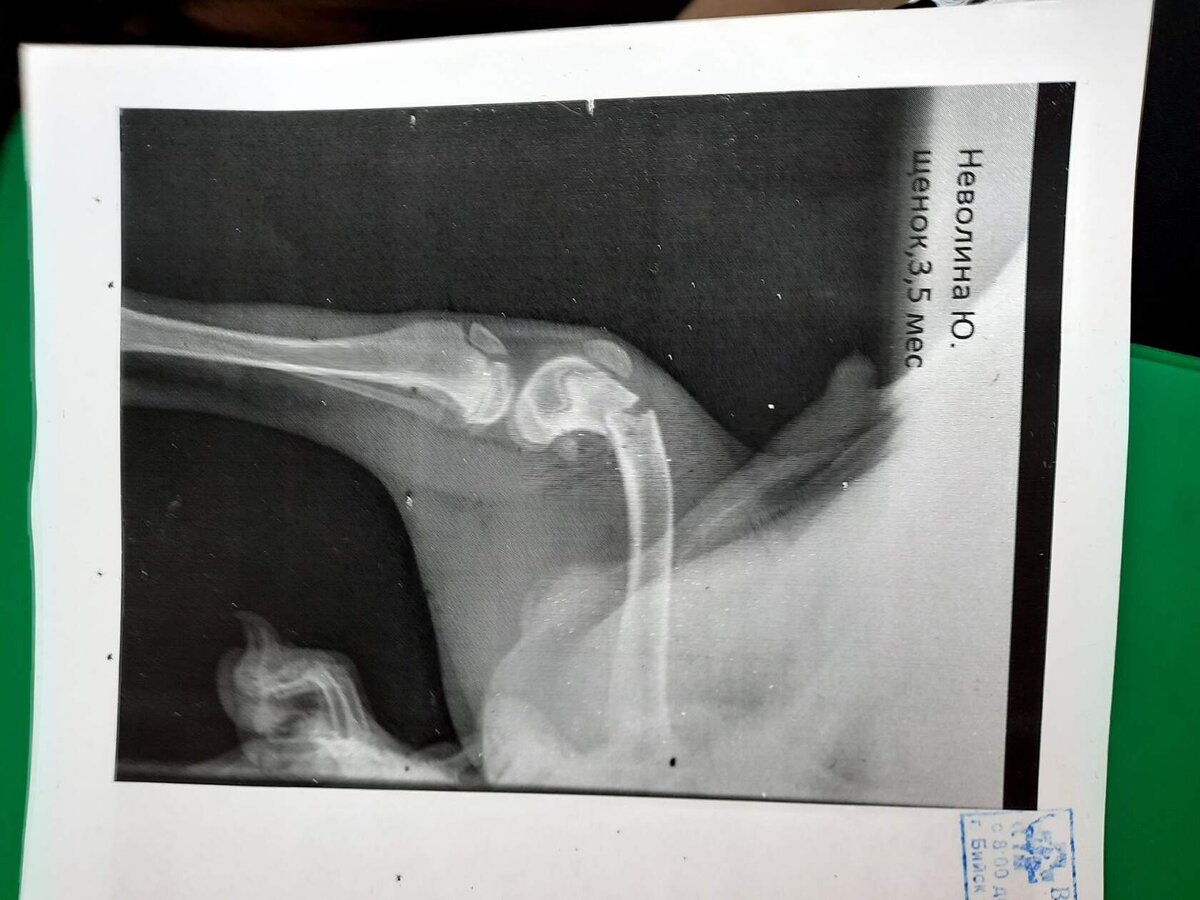

После падения с третьего этажа, он кричал как ребенок. Плакал от любой попытки пошевелиться. Мы давали ему обезболивающее, чтобы щенок хоть немного поспал. Кушал и пил, как первый раз. Бедный, наголодался. Как начала работать клиника, сразу поехали туда. Кроме ушибов и гематомы, сломана лапка в 2-х местах. "Родился в рубашке", подумала я, когда увидела снимок.

Наложили Дику гипс и поехали домой

Наложили Дику гипс и поехали домой залечивать раны. Несколько дней мы еще не спали. Полет с третьего этажа, удар, хорошенько отбили грудную клетку Дику. Щенок кашлял и плакал.